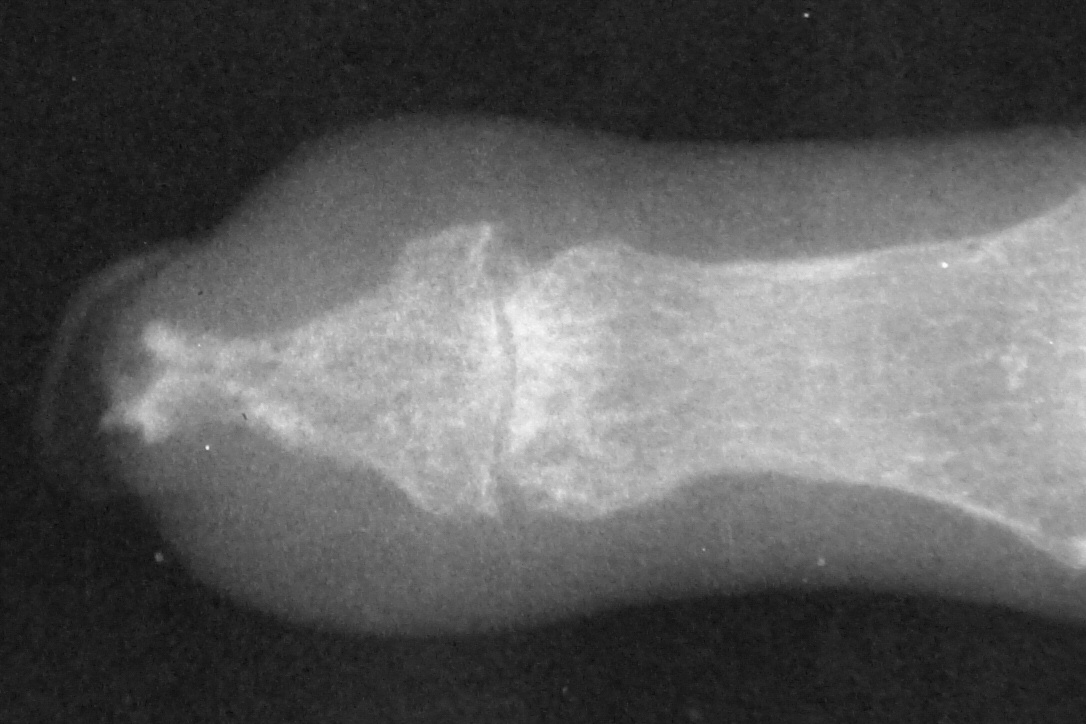

Xrays over this period: initial deformity, bone graft, and progressive bone graft loss over the course of years:

Image Image